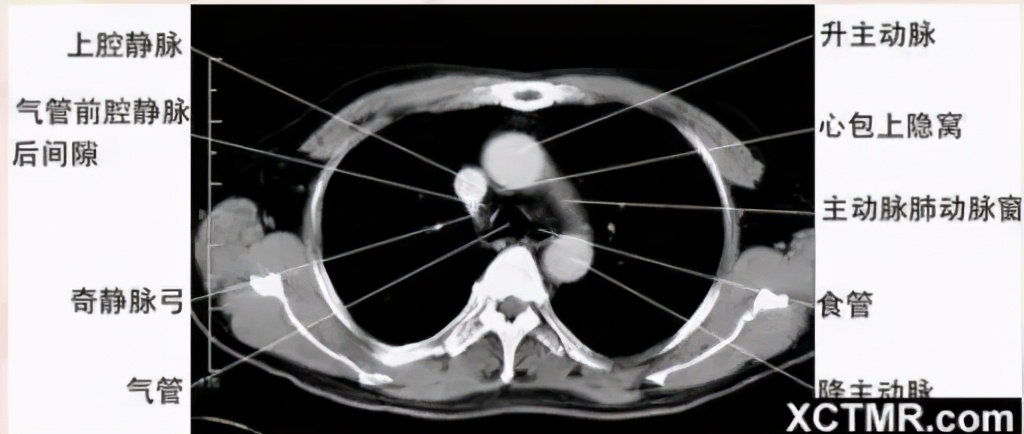

主肺动脉窗层面